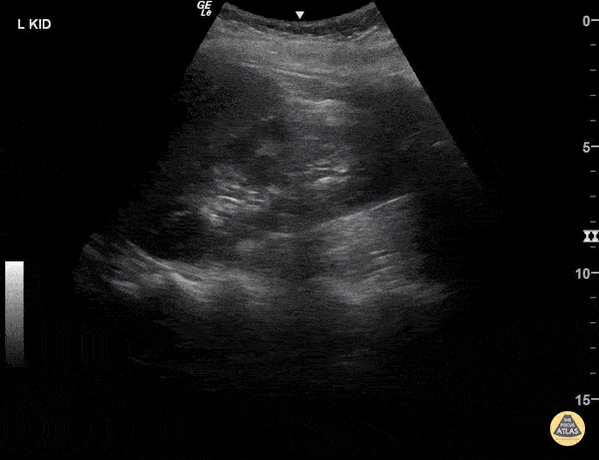

13 - Normal kidney

14 - Moderate hydronephrosis